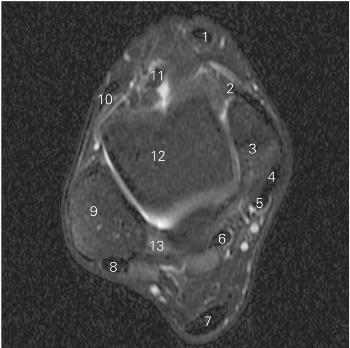

图5-36 经远侧胫腓关节的横断层 MR T2WI FS

1 胫骨前肌 tibialis anterior 2 胫骨 tibia

3 胫骨后肌 tibialis posterior

4 趾长屈肌 flexor digitorum longus

5

长屈肌 flexor hallucis longus 6 跟腱 tendo calcaneus

7 腓骨短肌 peroneus brevis 8 腓骨长肌 peroneus longus

9 下胫腓后韧带 posterior lower tibiofibular ligament

10 腓骨 fibula

11 胫腓远侧关节 distal tibiofibular joint

12 下胫腓前韧带 anterior lower tibiofibular ligament

13 趾长伸肌 extensor digitorum longus

14

长伸肌 extensor hallucis longus